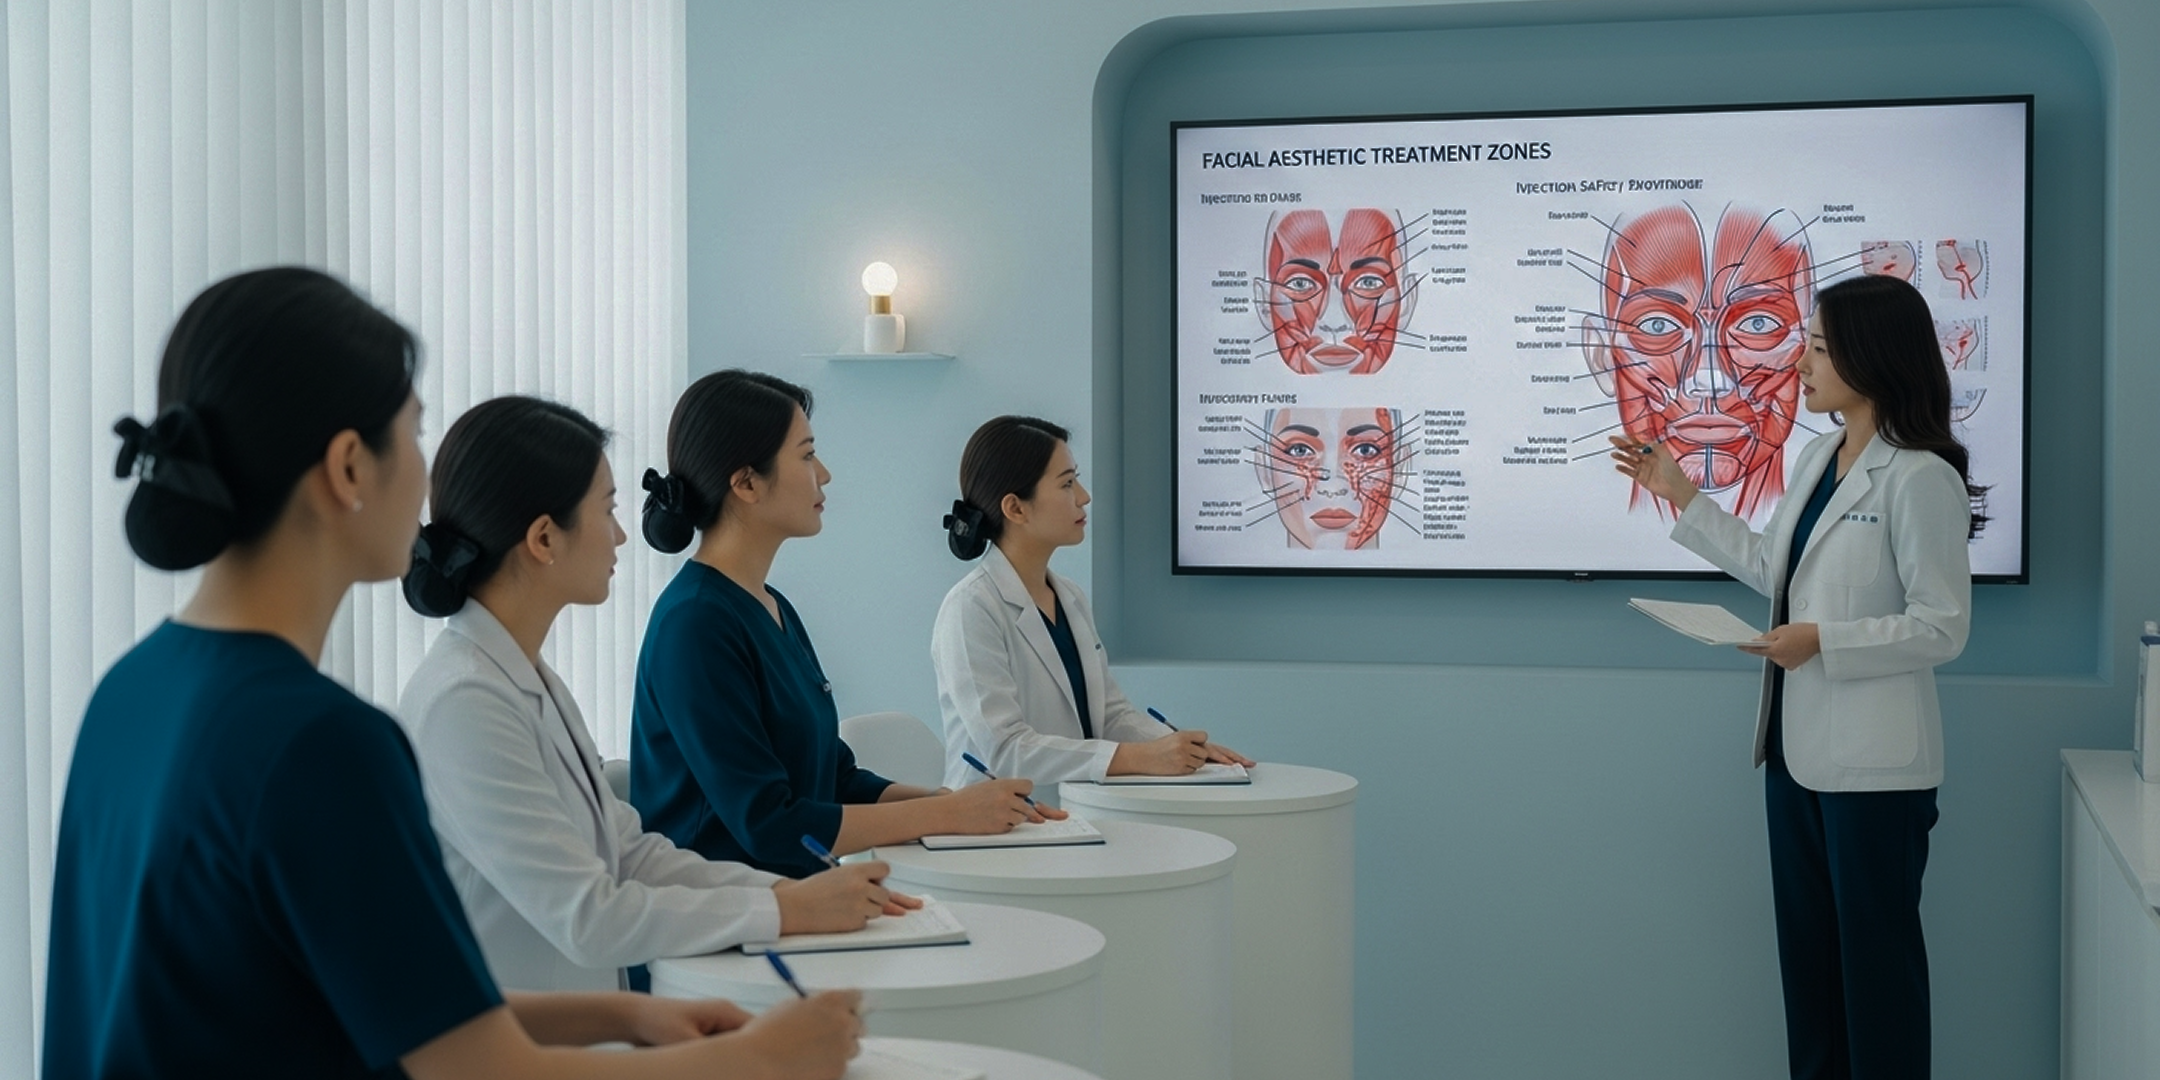

OCTOBLUEは韓国の美容医療市場で蓄積した15年以上のコンサルティング経験を 基に、各クリニックのニーズに合った最適な美容医療メニューをご提案します。 専門のコンサルティングチームが直接訪問し、クリニックの構造を含めた 環境と運営方針を把握した上でカスタマイズしてアドバイスします。

Medical Master Class Process

Seminar

韓国形成施術の最新トレンド、手術技 法、使用機器および材料に関する 教育を行います。